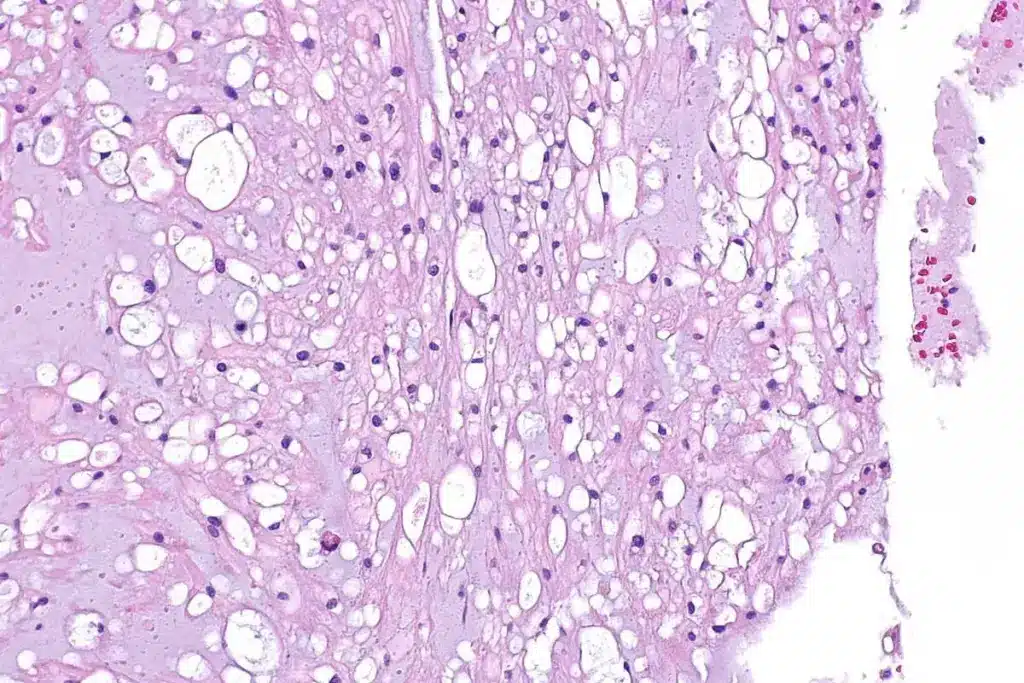

Biopsy and Histopathological Timeline Indicators

Biopsy results tell a lot about the tumor, like how aggressive it might be. Looking at the tissue under a microscope can show how fast SCC is growing.